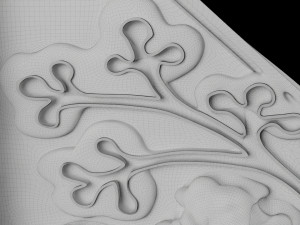

Breast anatomy histology detailed labelled precise to scale model 3D Модель

This is a 1:1 scaled model of right breast cut opened in sagittal plane to reveal its internal antomy and histology (schematic). The deeper parts and fascial layers are also depicted to give a very detailed approach to the model. The full layers starting from skin, nipple areola, till intercodtal muscles and ribs are also depicted.